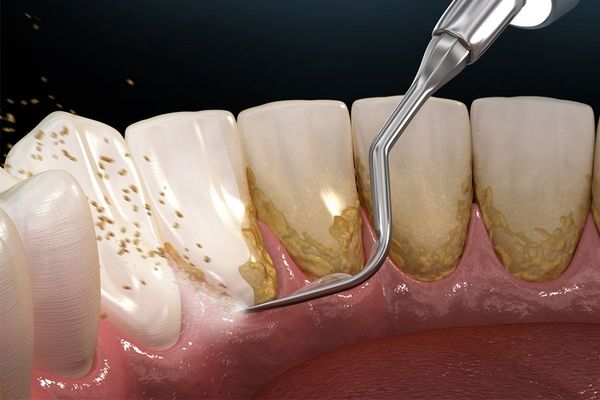

Vôi răng không thể làm sạch bằng bàn chải thông thường, mà cần đến nha sĩ để loại bỏ bằng máy cạo vôi chuyên dụng.

Tại Nha khoa Mira, chúng tôi sử dụng máy cạo vôi siêu âm hiện đại, giúp loại bỏ mảng bám hiệu quả mà không gây ê buốt hay tổn thương mô nướu. Quá trình cạo vôi thường diễn ra trong 15–30 phút, nhẹ nhàng và an toàn.